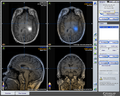

Project Title: Generation of a hybrid MR-Spectroscopic (MRS) dataset under 3DSlicer

Generating a hybrid MR-Spectroscopic (MRS) dataset under 3DSlicer that can be used for fusion with the anatomic dataset under iPlan of BrainLAB in AMIGO. A hybrid MR-Spectroscopic dataset can for example be used for biopsy targeting in brain tumors. Besides, the metabolic concentrations and ratios can help to diagnose lesions.

Loaded/integrated processed chemical shift-MRS data from Uni. Marburg into Slicer4.